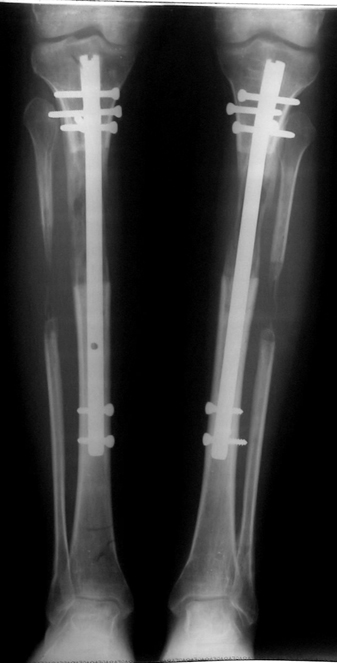

The application of the external fixator: Three Schanz screws are placed distally and three screws are placed proximally. At least 1 mm of distance shall remain between the screws and the nail.

Postoperative care: Distraction is commenced at day 10. 0,25 mm of lengthening is perfomed 4 times daily (every 6 hours). Hip and knee joint motion exercises begin at 1-2. day postoperatively. For many years, the treatment of lower extremity shortness has been very hard for the patient and the surgeon. The techniques developed after the introduction of Ilizarov’s distraction osteogenesis concept have pioneered a new era, and have been considered to be procedures in which previous complications are encountered much less frequently.

In selected cases, we prefer to use a combination of a unilateral dynamic axial fixator and an interlocked intramedullary nail, in order to protect the length and alignment after the completion of the lengthening procedure. As a prerequisite for this technique, the narowest diameter of the medullary cavity shall be wider than 7 mm and the length of the nail segment distal to the osteotomy site shall be at least 8 cm. after the completion of the lengthening procedure.The intramedullary nail neutralizes shear and bending forces on femur during lengthening, shortens external fixation time, and protects newly formed bone against fractures. In our series, subtrochanteric osteotomy was performed in one case. No varus angulation occured despite the intramedullary nail.

Ilizarov stressed the significance of endosteal blood circulation for distraction osteogenesis. Although we placed the intramedullary nail after reaming the femur in all cases, the time for callus formation was not longer than expected. Thus we found that there is no slowing in the rate of new bone formation due to disruption of medullary blood flow. The rationale of this finding is revascularization that occurs following reaming of the medullary cavity, the fixation stability with the intramedullary nail and early functional weight bearing. The potential disadvantages of a combined use of external and internal fixation metods are increased blood loss, intramedullary infection, risk of fat embolism and excessive metal load.The most fearsome complication is a deep intramedullary infection (panosteomyelitis) triggered by pin tract infection.No such complication was encountered in our series. In order to avoid this complication, after the completion of lengthening the nail shaill be interlocked from the medial side, and contact of internal and external fixator pins shall be avoided.